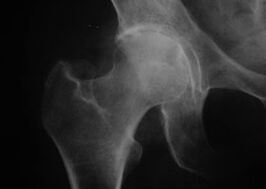

Εμφάνιση άρθρωσης με οστεοαρθρίτιδα

Κοξάθρωση, αρθροπάθεια της άρθρωσης του ισχίου

Με τη νόσο αυτή παρατηρείται κλασική κλινική εικόνα οστεοαρθρίτιδας.

Το πρώτο σύμπτωμα της κόξαρθρωσης είναι η ενόχληση στην άρθρωση του ισχίου μετά από φυσική δραστηριότητα.

Καθώς η κόξαρθρο εξελίσσεται, ο πόνος αυξάνεται, εμφανίζεται δυσκαμψία και περιορισμένη κινητικότητα.

Οι ασθενείς με σοβαρή μορφή κόξαρθρωσης προστατεύουν το πάσχον άκρο, αποφεύγουν να το πατούν και, όταν στέκονται ακίνητοι, επιλέγουν θέσεις στις οποίες ο πόνος είναι λιγότερο αισθητός.